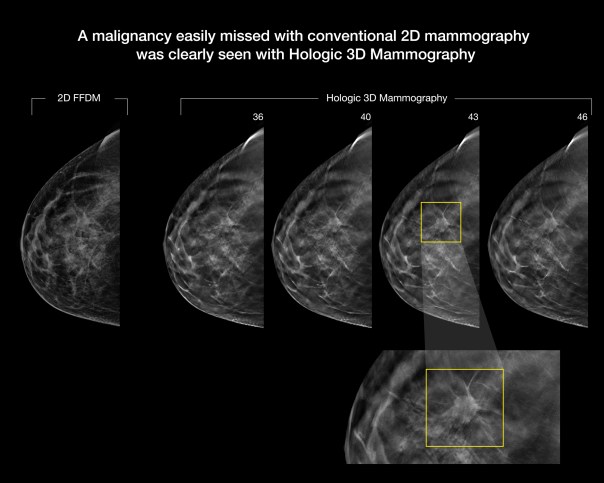

The breast is a three-dimensional object composed of different structures located at different heights within the breast. These structures can overlap and cause confusion when viewed as a flat two-dimensional image. This confusion of overlapping of tissue is a leading reason why small breast cancers may be missed and normal tissue may appear abnormal, leading to unnecessary callbacks. Using breast tomosynthesis technology, the Hologic system creates a 3-dimensional image of the breast structure, which enables radiologists to more clearly see through overlapping tissue to detect cancers, often at an earlier stage.

Mammograms with this technology include both 2D images and tomosynthesis scans. During the tomosynthesis portion of the exam, an X-ray arm sweeps in a slight arc over the breast, taking multiple images. A computer then converts the images into a stack of thin layers, allowing the radiologist to review the breast tissue one layer at a time.